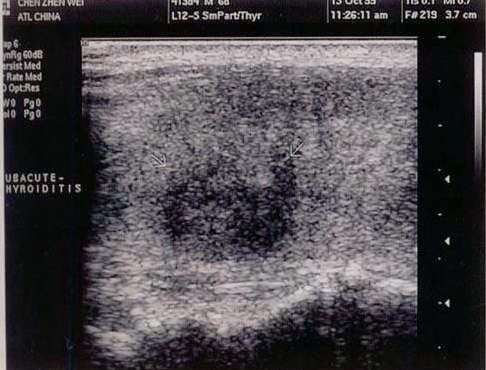

D.境界不规整,回声较弱